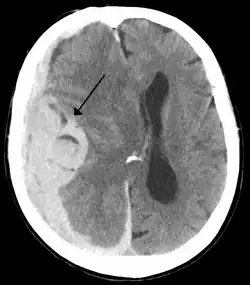

Die Mittellinienverlagerung (auch Mittellinienshift) ist die Verschiebung des Gehirns über die Mittellinie des Schädels.[1] Sie wird durch eine Raumforderung verursacht und kann mittels Schnittbildgebung dargestellt werden. Als Zeichen eines deutlich erhöhten Hirndrucks ist sie allgemein ein ungünstiges prognostisches Zeichen. Die Therapie erfolgt, abhängig von der Schwere der Verschiebung und der Ursache, mit abschwellenden Medikamenten und/oder einer chirurgischen Entlastung.

Eine Mittellinienverlagerung kann bildgebend dargestellt werden, dabei kommen vor allem schnittbildgebende Verfahren wie die Computertomografie (CT) und Magnetresonanztomographie (MRT) zum Einsatz.[1] Das CT ist Goldstandard in der Diagnostik,[2] weist jedoch nur eine Sensitivität von etwa 81 % und eine Spezifität von etwa 43 % für das Vorliegen von erhöhtem Hirndruck auf.[3]

Die Mittellinienverschiebung wird üblicherweise in Millimeter seitlicher Abweichung gemessen.